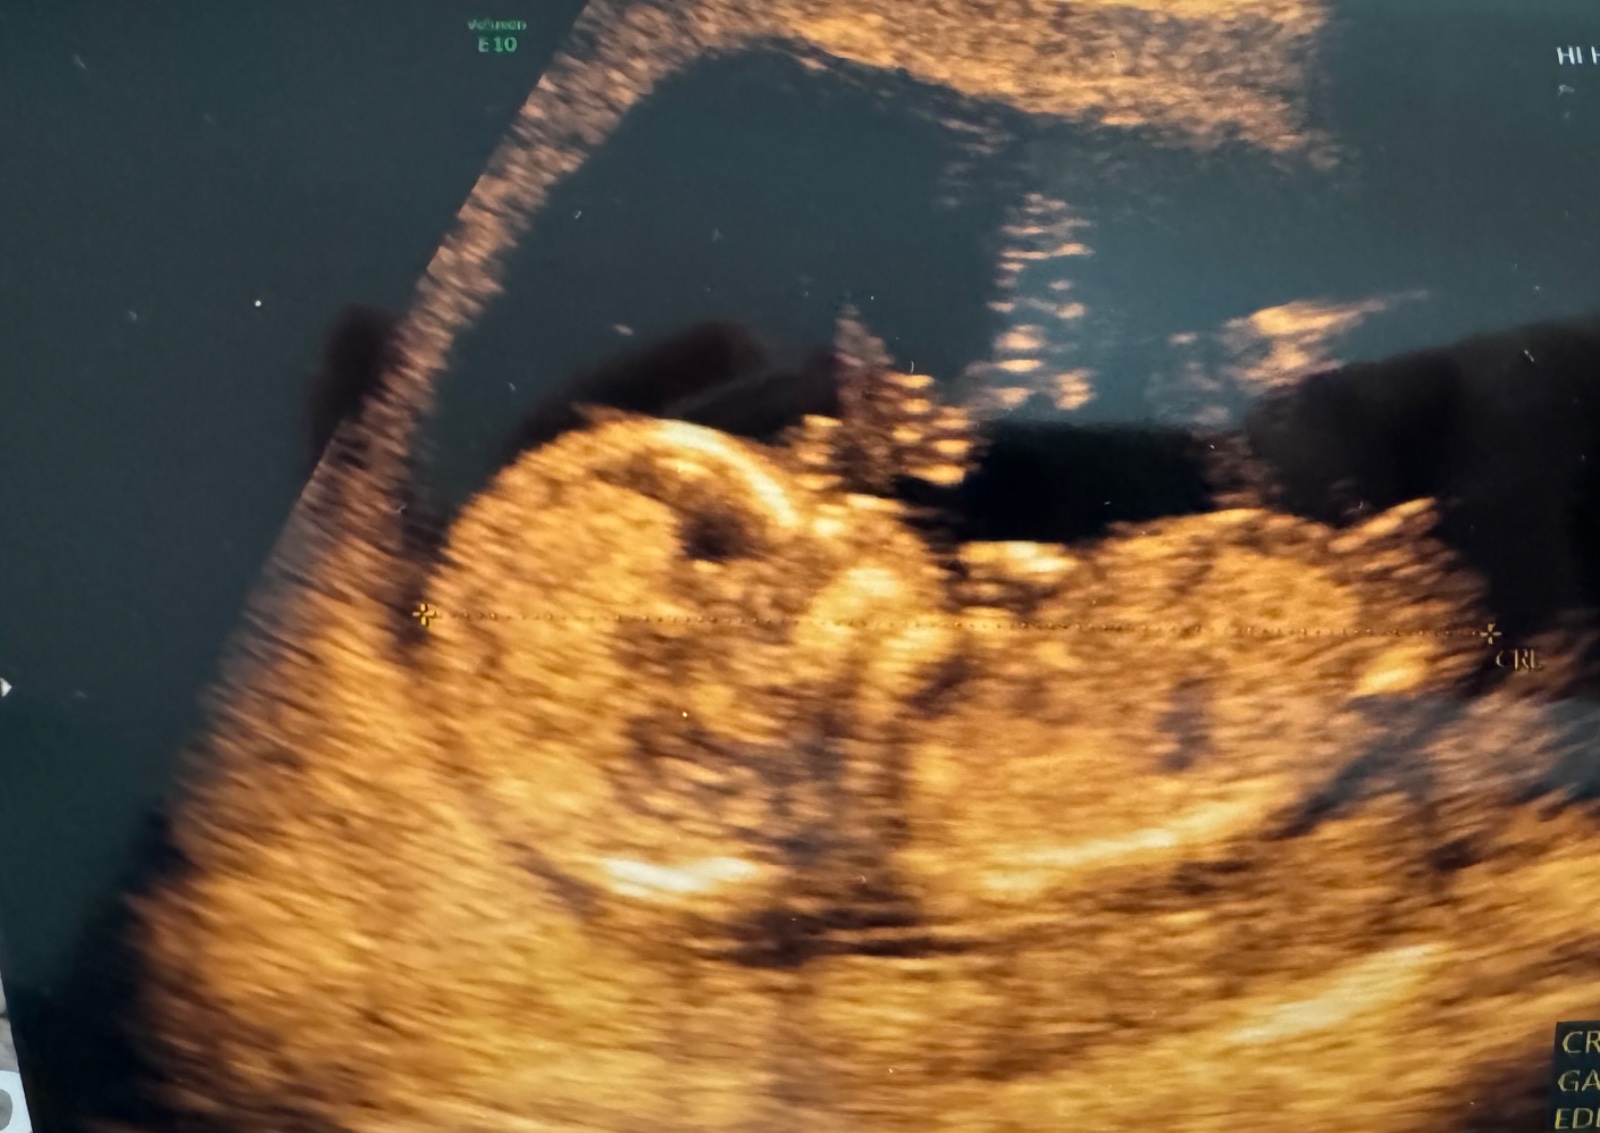

Ahoj, ráda bych se zeptala jaké pohlaví na utz vidíte? Zda to někdo pozná🙏🏻 děkuji 🙂

Taky tipuji holčičku, pohlavní hrbolek jde vodorovně 🙂

Mám skoro stejnou fotku a taky čekám zda to bude holka nebo kluk 😁 když vidím Vaší řekla bych holka 🙂 já u své fotky každý den měním názory a to je stejná, řekla bych 🤣

Rekla bych holcicka